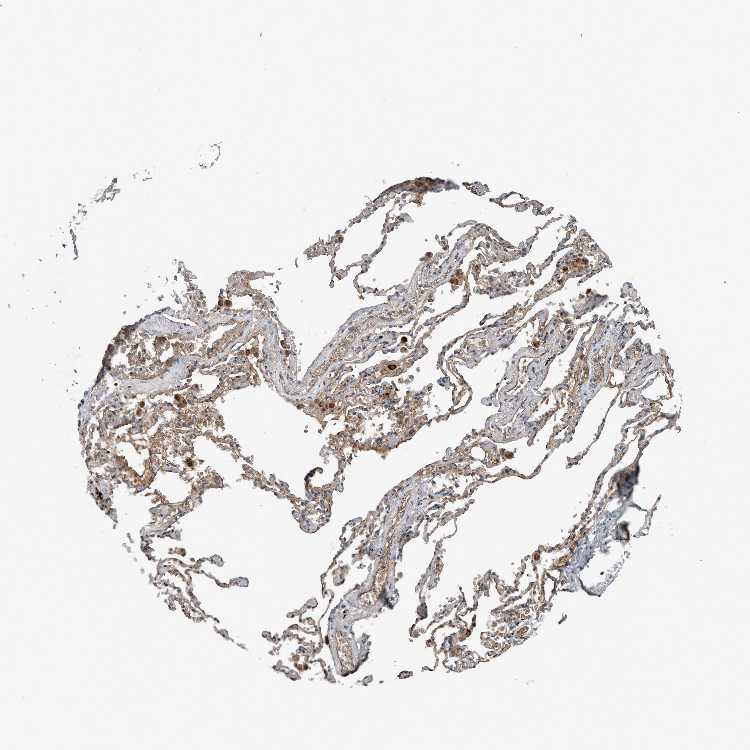

SOFT TISSUE 1 - Antibody stainingi

Antibody staining in the annotated cell types in the current human tissue is reported as not detected, low, medium, or high, based on conventional immunohistochemistry profiling in selected tissues. This score is based on the combination of the staining intensity and fraction of stained cells.

Each image is clickable and will lead to virtual microscopy that enables deeper exploration of all samples and also displays staining intensity scores, fraction scores and subcellular localization as well as patient and tissue information for each sample.

Antibody HPA026904

Fibroblasts Medium

Peripheral nerve Not detected